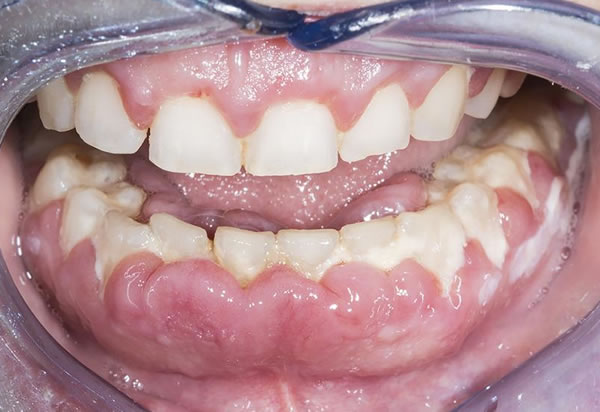

Evaluación de encías

Con el tacto y la vista, el dentista busca signo de inflamación en las encías, que puedan indicarle en cuál diente se localiza la pulpitis y si hay presencia de alguna infección o absceso.